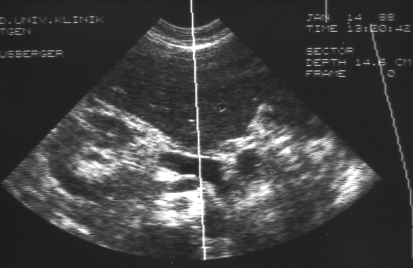

Die Abdomensonographie ist als Screeninguntersuchung und für eine routinemäßige Verlaufskontrolle bei Aneurysmen gut geeignet. Zur exakten Bestimmung der Größe und Morphologie wird jedoch eine Computertomographie (Abb. 1), in Ausnahmefällen eine Magnetresonanztomographie, durchgeführt.

Abbildung 2: Duplex Ultraschall bei Nierenarterien Stenose rechts